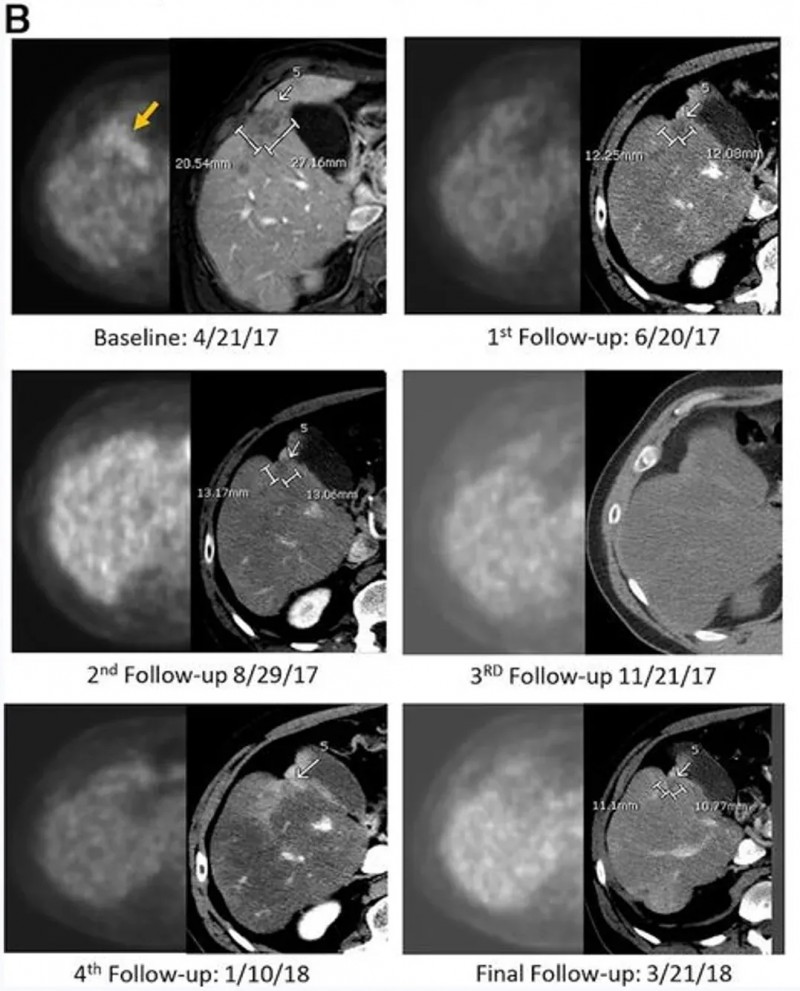

结果显示:CAR-T输注6周后,正电子发射断层扫描(PET-CT)提示肝脏内原氟脱氧葡萄糖(FDG)阳性病灶完全无代谢活性,该完全代谢反应持续13个月;静脉增强CT显示目标病灶稳定或略缩小,无新增转移灶。治疗3.7个月时,PET扫描显示肝脏仍维持无代谢活性,但胰头原发灶代谢活性升高,患者随即接受胰腺肿块放疗(以5-氟尿嘧啶为放射增敏剂),后续扫描显示原发肿瘤灶亦达完全代谢缓解。该患者总生存期(OS)长达23.2个月——而多数IV期胰腺腺癌患者中位生存期仅5个月,意味着CEA CAR-T疗法让这位化疗耐药患者的生存期延长近5倍(4.64倍)。

▲图源“JITC”,版权归原作者所有,如无意中侵犯了知识产权,请联系我们删除